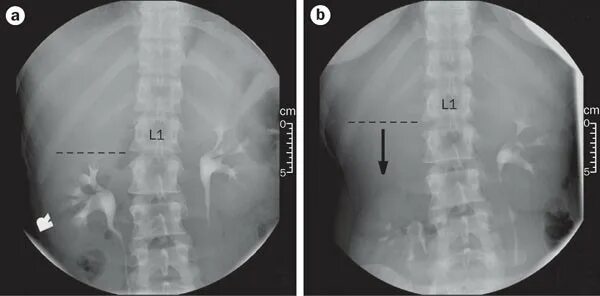

Нефроптоз 2 степени что это